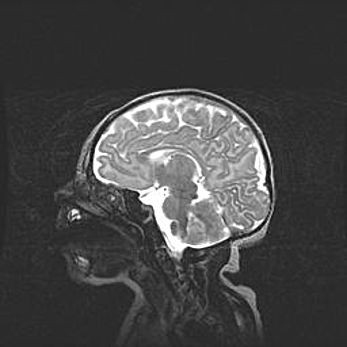

Открытая гидроцефалия.

Возраст: 9 месяцев 12 дней

Вес: 6800 г

Пол: мужской

Окружность головы: 41,5 см

Срок гестации: 28 недель

Гидроцефалия головного мозга у новорожденных имеет характерный признак: опережающий рост окружности головы приводит к визуально хорошо определяемой гидроцефальной форме сильно увеличенного в объёме черепа. Детские неврологи определяют следующие симптомы гидроцефалии у грудничков: выбухающий напряжённый родничок, частое запрокидывание головы, смещение глазных яблок к низу.